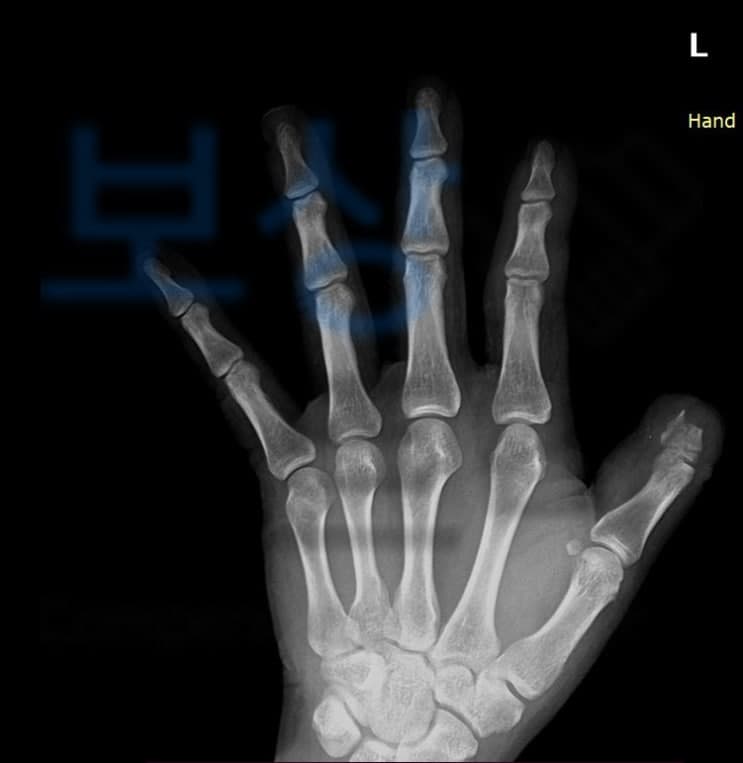

특히 제조업에서 기계에 끼이거나 눌리거나 부딪히는 사고로 인해 손가락 골절, 절단과 같은 재해가 발생하는데요, 오늘은 손가락 골절 및 절단으로 신체에 남게 될 수 있는 장해에 대해 산재 약관은 어떻게 기술되어 있는지, 그리고 보상파트너의 도움을 받아 올바른 산재보상금 받으신 김@@님의 보상 사례도 소개해드리겠습니다.

손가락골절 및 절단으로 인해 대다수 분들이 핀으로 고정하는 금속 고정술을 받으시거나 손가락 접합수술을 받습니다. 이때 손가락이 골절된 단면이나 부위가 좋지 좋지 않은 경우 손가락 절단술을 시행하기도 하며 접합을 하였더라도 괴사가 진행되는 경우에도 손가락 절단술을 시행 할 수 밖에 없습니다.

산재 장해 약관에서 손가락의 장해는 2가지 항목으로 구분하여 판정합니다. 바로 손가락의 결손 장해와 기능 장해의 정도에 따라 장해등급이 결정되어 산재보상금이 달라집니다.

결손장해는 손가락이 절단되어 상실된 장해를 의미합니다. 손가락이 얼마나 절단되었는지에 따라 손가락을 잃은 사람과 지골의 일부를 잃은 사람으로 구분됩니다. 간혹 손가락이 절단돼서 손가락을 잃었다고 생각하시는 환자분들이 계시는데요,

손가락이 절단되었어도 산재 장해약관에 부합하지 않는다면 그저 지골의 일부를 잃은 사람으로 적용되어 장해등급을 결정받게 되고 반대로 지골의 일부를 잃은 사람이어도 상황에 따라 결손장해가 아닌 기능장해로 평가하여 더 높은 산재보상금을 받으실 수 도 있습니다.

기능장해는 손가락 관절의 운동제한 및 상실의 정도에 따라서도 등급을 인정합니다. 손가락 골절 및 접합수술로 움직이는게 예전처럼 되지 않아도 산재 약관상 기능 장해에 해당되지 않거나 또 운동 가능 영역 측정 시 잘못된 측정방법을 적용하여 올바른 장해등급을 받지 못하는 경우도 발생할 수 있습니다.